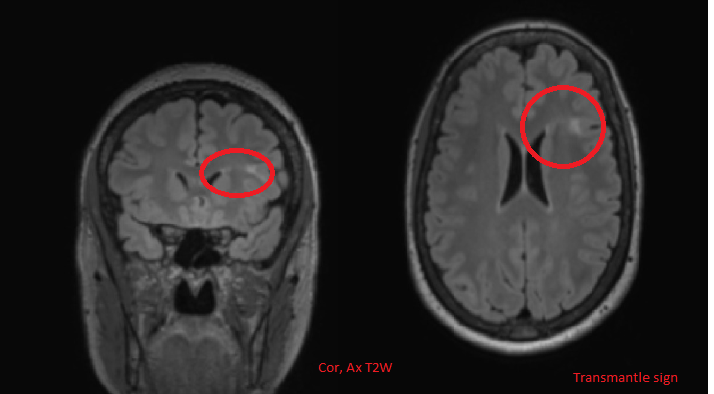

Focal cortical dysplasia is another cause of seizures, esp if it occurs in the frontotemporal lobes. What are some general features of FCD?

Blumcke classification of focal cortical dysplasia (2011). Types 1 to 3

cortical thickening

blurring of white matter-grey matter junction with abnormal architecture of subcortical layer

T2/FLAIR signal hyperintensity of white matter with or without the transmantle sign

T2/FLAIR signal hyperintensity of grey matter

abnormal sulcal or gyral pattern

segmental and/or lobar hypoplasia/atrophy

there is no oedema, calcification, or contrast enhancement